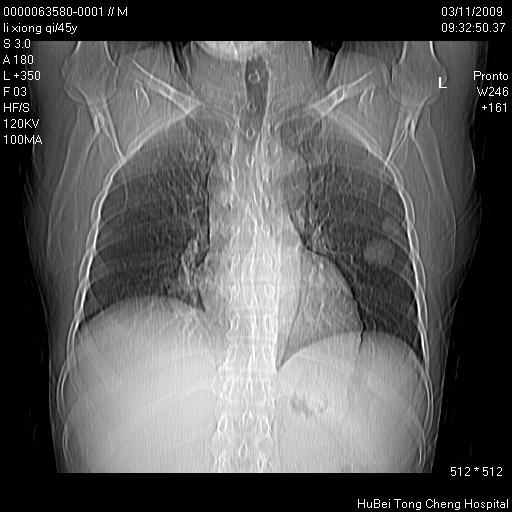

患者 男,45岁。胸痛,咳嗽伴痰中带血1月余。

临床诊断:肺结核?

胸部ct轴位平扫(层厚10mm,螺距1.5,重建间隔10mm),图像如下: